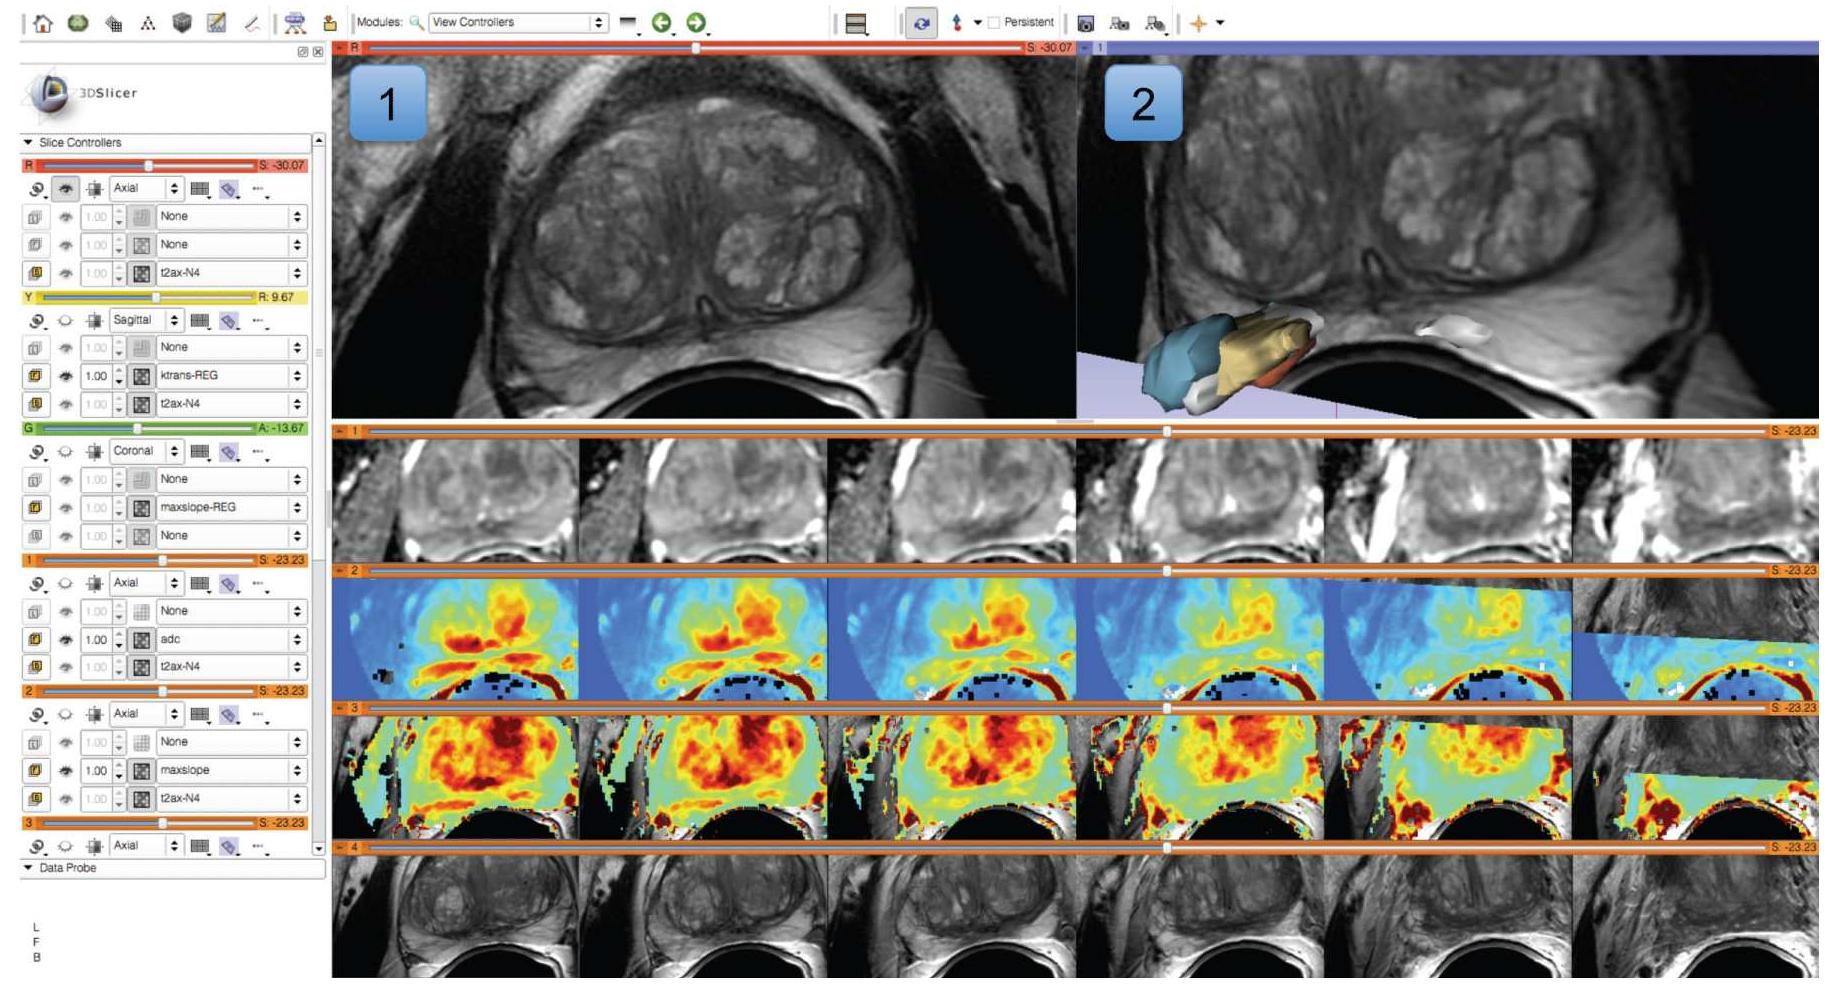

Quantitative analysis has tremendous but mostly unrealized potential in healthcare to support objective and accurate interpretation of the clinical imaging. In 2008, the National Cancer Institute began building the Quantitative Imaging... more